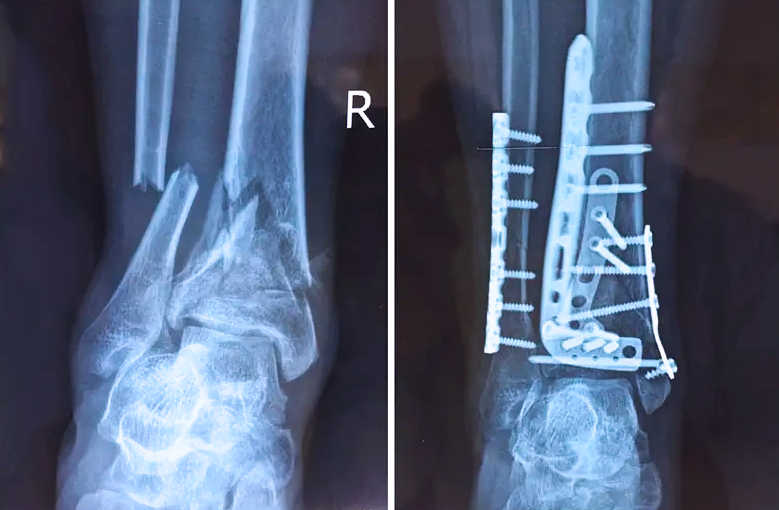

對于骨科醫生而言,關節外的骨折是相對比較簡單的,因為關節外的骨折允許我們復位的時候有一些偏差,但是如果骨折部位在關節內,我們就不能有任何的偏差。而且關節內的骨折是有關節面的,如果關節面不平整,就會導致患者以后出現創傷性關節炎等癥狀,或者出現長期的疼痛,甚至造成殘疾。所以對于關節內的骨折,一定要做到“解剖復位”,就像搭積木一樣,每個積木塊、每個碎骨塊都要完好的拼到一起,做到嚴絲合縫。

踝關節是人體中負重較大的關節,也是活動度較大的地方,所以對于足踝部位的關節內骨折,我們更需要做到“解剖復位”。對于這種關節內的骨折,尤其是踝關節內部的骨折,不僅需要進行X影像平片正側位的拍攝,由于在二維影像上無法判斷關節面的受損情況,往往還需要進行三維影像的檢查。

在術前,我們需要做三維掃描的CT檢查,我們必須要有CT的片子,還要有三維的重建。

在術中,我們怎么去判斷關節面平不平整呢?常規的正側位影像是不能判斷的。有些醫生為了準確的判斷,可能會選擇做開放性的手術,把關節暴露出來,在眼睛的直視下判斷關節面平不平整。但是關節全部打開,無疑增加了病人的創傷,而且增加了患者的恢復時間。所以如果在術中我們有三維影像的支持,對醫生做手術而言就會事半功倍,而且能夠大大的增加手術準確度,增加患者術后的預后。所以在術中有三維影像的支持是非常必要的!